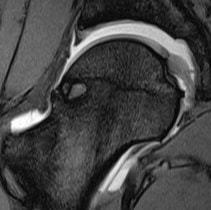

Zur Vorbereitung von Hüftgelenksoperationen ist die Kenntnis des Knorpelzustands im Bereich des Kopfes des Oberschenkelknochens und der Gelenkpfanne bzw. des Zustands des Kopfbands eine wesentliche Voraussetzung, um unter Bezugnahme auf die örtliche Ausdehnung eines festgestellten Gelenkschadens beispielsweise einen günstigen arthroskopischen Zugangsweg festlegen zu können.

Um sich mit Hilfe einer Magnetresonanztomographie ein gutes Bild über die örtliche Erstreckung und Grösse eines allfälligen Gelenkschadens machen zu können, ist es vorteilhaft, das Hüftgelenk mit einem Kontrastmittel zu füllen und während der Untersuchung einer Zugbelastung zu unterwerfen.

Bevor nun die Traktion zur Anwendung kommt, muss der Fuss der Gegenseite auf einer Abstützplatte positioniert werden, um eine Beckenkippung und einen damit einhergehenden Kraftverlust zu verhindern. Ohne den Patienten zu beeinträchtigen, wird der Gelenkraum durch die angewendete Zugkraft erweitert und ermöglicht dadurch eine Beurteilung der zentralen Anteile des Hüftgelenks. Mit Hilfe dieser Methode können Läsionen am Gelenksknorpel sowie pathologische Veränderungen am Labrum acetabulare und am Ligamentum capitis femoris erstmals exakt detektiert werden.